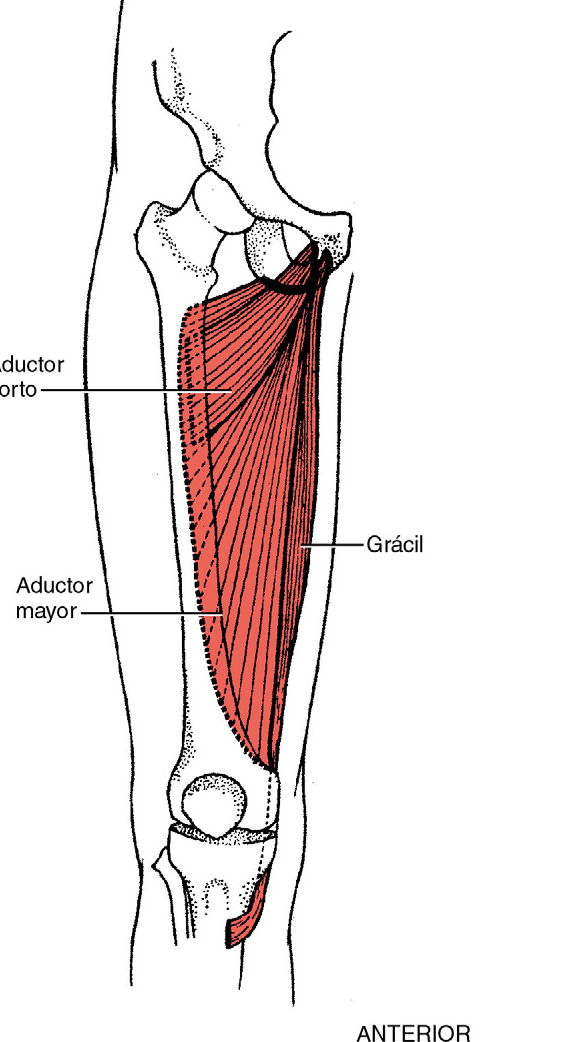

Aducción de la cadera

Amplitud de movimiento: 0 a 15-20 grados

Músculos

Aductor mayor

Aductor corto

Aductor largo

Pectíneo

Grácil

Grados 5 ( normal ), 4 ( bueno ) y 3 ( regular )

Posición del paciente: decúbito lateral con la extremidad inferior que se somete a la prueba, apoyada en la camilla. El terapeuta sostiene la extremidad inferior contraria a 25 grados de la abducción, colocando su antebrazo en la pierna y la mano en la cara interna de la rodilla

Posición del terapeuta: de pie detrás del paciente a la altura de la rodilla. La mano que aplica resistencia se coloca en la cara interna del fémur distal, la resistencia en dirección hacia abajo

Prueba: el paciente aduce la cadera hasta que la extremidad inferior situada debajo contacta con la extremidad inferior situada en la parte superior

Instrucciones al paciente: levante la extremidad inferior de abajo hasta alcanzar la que esta arriba. No me deje bajarla.

Gradación

Grado 5 ( normal ) el paciente completa toda la amplitud de movimiento disponible y mantiene la posición final contra resistencia máxima

Grado 4 ( bueno ) el paciente completa toda la amplitud de movimiento disponible y mantiene la posición final contra resistencia de intensa a moderada

Grado 3 ( regular ) el paciente completa toda la amplitud de movimiento pero no soporta resistencia

Grado 2 ( deficiente )

Posición del paciente: decúbito supino, la extremidad inferior contraria a la prueba se coloca en ligera abdcción

Posición del terapeuta: de pie en el lado de la extremidad inferior que se somete a la prueba, a la altura de la rodilla. Con una mano sostiene el tobillo, con la mano contraria palpa la masa de los aductores

Prueba: el paciente aduce la cadera sin rotación

Instrucciones al paciente: mueva la extremidad inferior hacia dentro acercándola a la otra.

Grado 2 ( deficiente ) el paciente aduce la extremidad inferior a lo largo de toda la amplitud de movimiento

Grados 1 ( vestigios de actividad ) y 0 ( nulo )